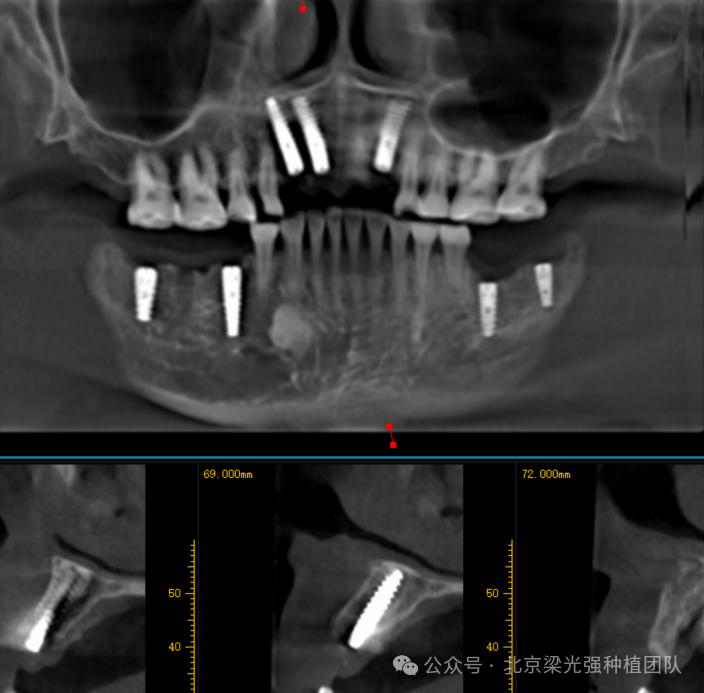

术后CBCT:

图片